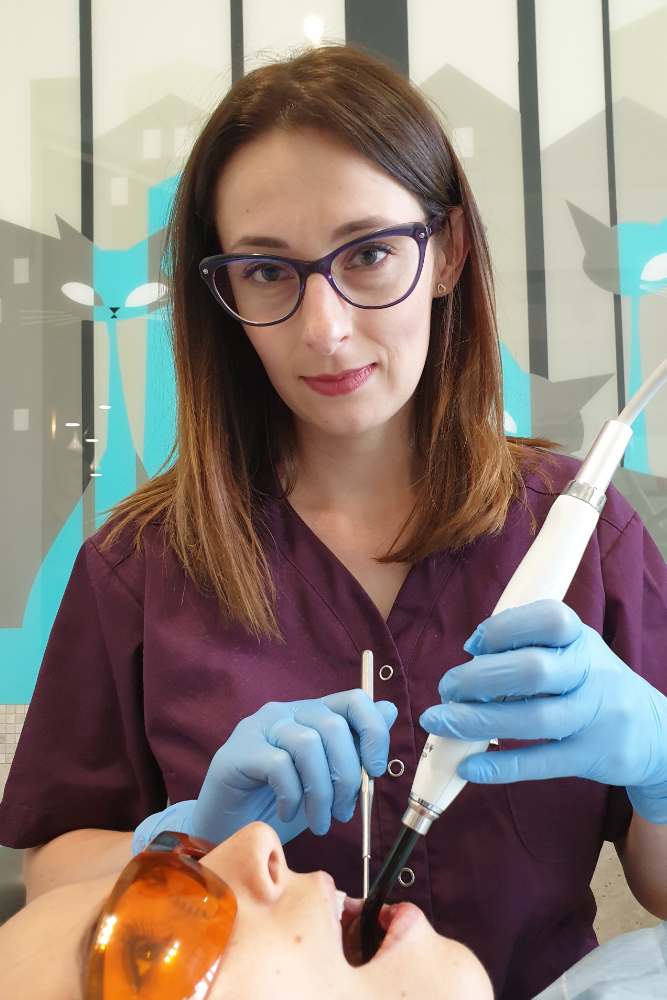

Lek. dent. Magdalena Wesołowska

Lek. dent. Aleksandra Szustkiewicz-Karoń

Lek. dent. Katarzyna Pilecka